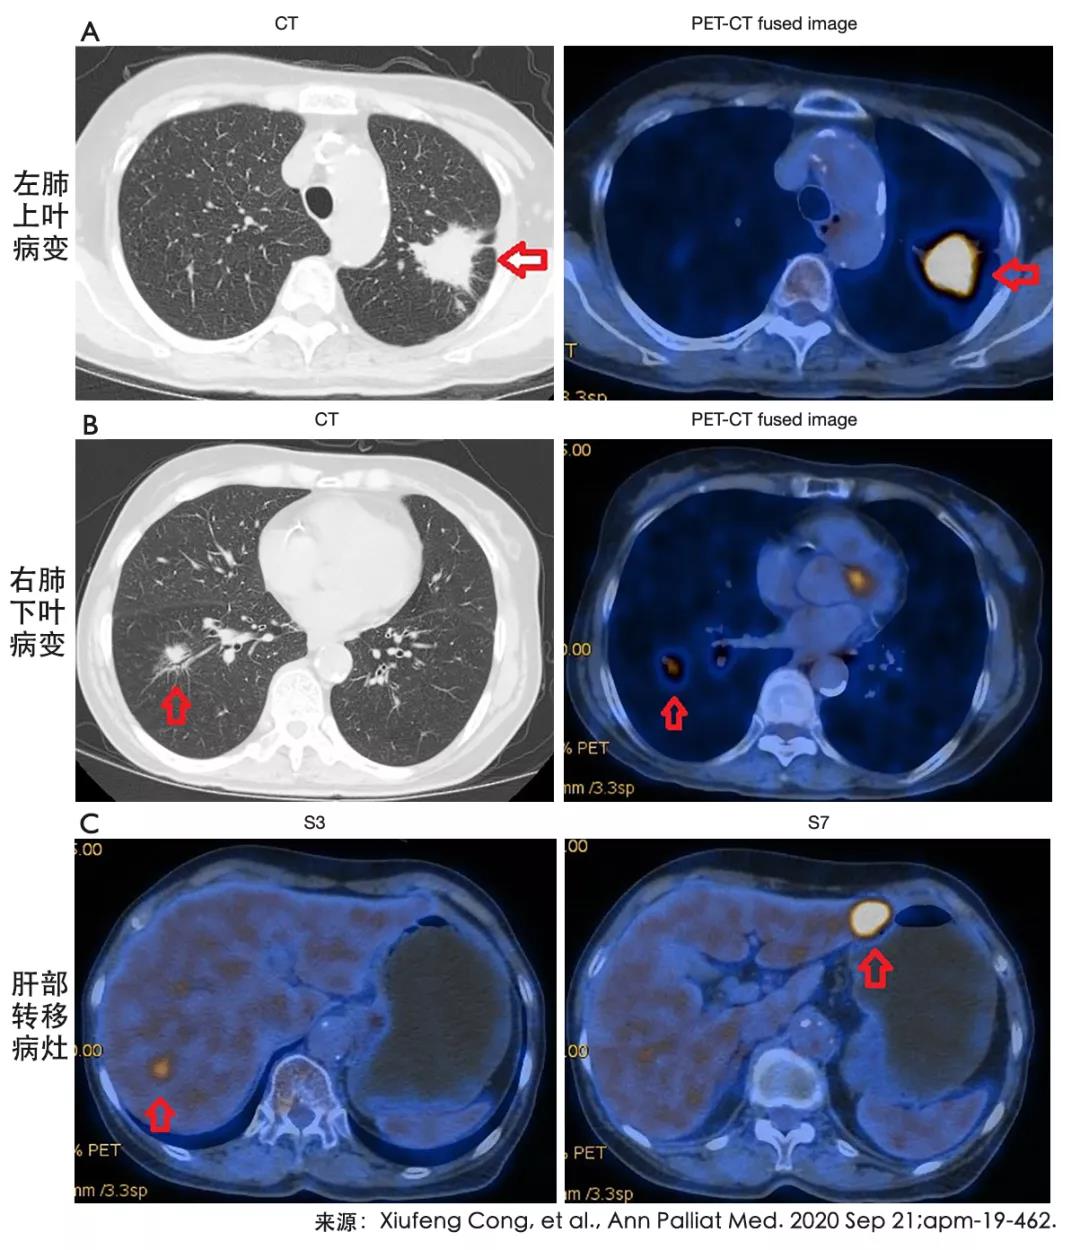

编者按本文摘选国际期刊的两篇最新研究进行摘要编译,揭示PD-L1表达及肝转移对免疫治疗疗效的影响,以及共突变类型对EGFR-TKI疗效的影响。PD-L1强表达患者...